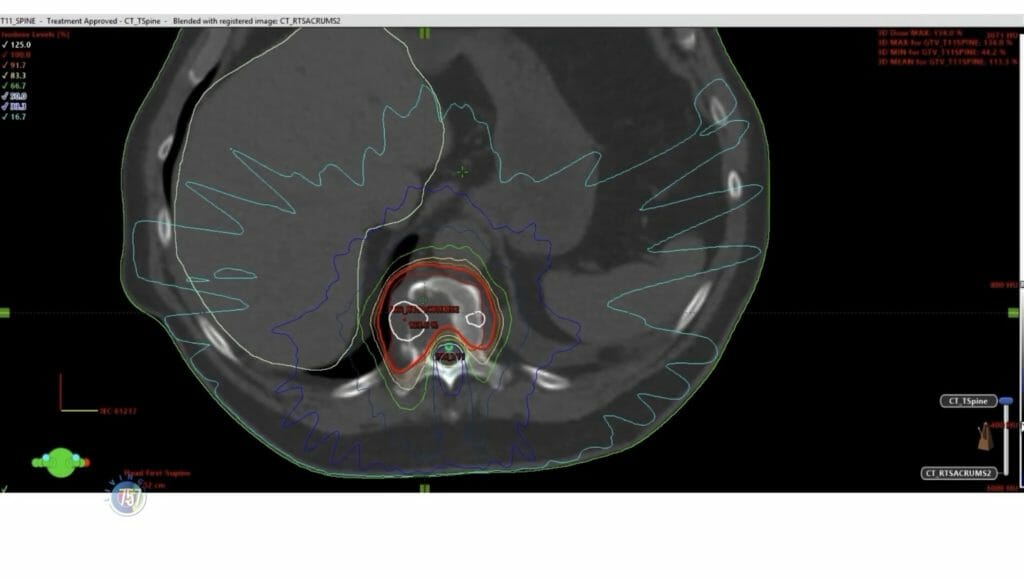

That’s when Gary met Doctor Ronald Kersh, a radiation oncologist at Riverside. When they met, Gary had stage 4 lung cancer, and had a tumor pop up in his spine. Dr. Kersh says that usually a patient with this diagnosis has about 6-7 months left to live.

The doctor treated Gary over a variety of areas with over 30 treatments, and over 2 and a half years later- Gary is still living with a good quality of life. But his story isn’t over, Dr. Kersh discovered another tumor- this time in Gary’s Brain.